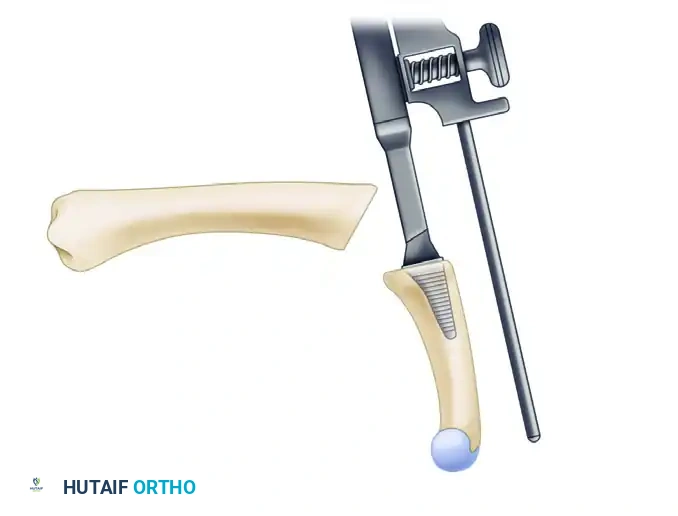

5. Kirschner Wire Placement and Construct Initiation

With the joint held in the optimal position, the tension band construct is initiated.

- Drill a transverse hole through the distal third of the proximal phalangeal neck using a 1.1 mm (0.045-inch) K-wire. This hole will serve as the distal anchor for the tension band wire.

- Pass a 24-gauge or 26-gauge stainless steel orthopedic wire through this transverse hole.

- Next, drive two longitudinal 1.1 mm or 1.6 mm (0.045-inch or 0.062-inch) K-wires in a retrograde fashion. Start at the dorsal base of the proximal phalanx, cross the prepared MCP joint interface, and advance into the metacarpal shaft. Ensure these wires cross proximal to the fusion site to provide rotational stability.

FIGURE 73-40E: Placement of a Kirschner wire in the distal third of the proximal phalangeal neck, completing the foundation of the tension band construct.